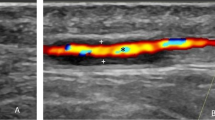

Aims We present our preliminary experience with the use of ultrasound in aiding the diagnosis of giant cell arteritis (GCA). Schmidt et alhave previously described a hypoechoic or ‘halo’ effect surrounding the walls of affected arteries on examination with ultrasound. We illustrate these features and explore the attributes and limitations of this technique.

Method Two groups of patients were recruited: (1) patients with suspected GCA awaiting temporal artery biopsy and (2) patients with no history or symptoms of GCA of a similar age group. All the recruited patients underwent ultrasound examination of both temporal arteries.